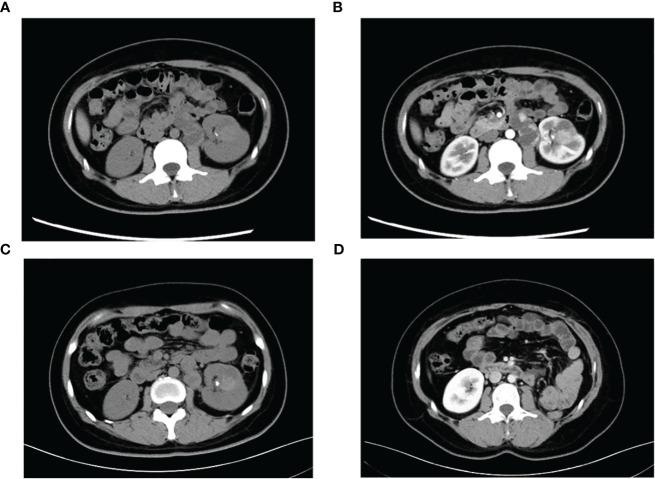

-rearranged renal cell carcinoma (RCC) is a rare subtype of renal tumor that primarily affects young women and is characterized by early metastasis and a poor prognosis. This case study presents a 29-year-old woman diagnosed with -rearranged RCC, who initially presented with painless gross hematuria. Computed Tomography (CT) imaging revealed the presence of a solid mass in the left kidney along with retroperitoneal metastasis. The patient received axitinib, a vascular endothelial growth factor receptor-tyrosine kinase inhibitor (VEGFR-TKI), as first-line neoadjuvant therapy. Subsequent testing confirmed positive expression of programmed death-1 protein L1 (), leading to the addition of tislelizumab, a PD1 inhibitor, to the treatment regimen. After 8 months, the patient's tumor size and metastases exhibited significant reduction, providing a favorable opportunity for subsequent surgical intervention. The tumor was classified as IV (pT3aN0M1) based on the pathologic stage of the American Joint Committee on Cancer (AJCC, 8th edition, 2017). The patient achieved long-term survival through combined systemic therapy involving surgery and neoadjuvant treatment. At the 30-month follow-up, there was no evidence of tumor recurrence or metastasis.

重排性肾细胞癌(RCC)是一种罕见的肾肿瘤亚型,主要影响年轻女性,其特征为早期转移和预后不良。本病例研究介绍了一名29岁被诊断为重排性RCC的女性,她最初表现为无痛性肉眼血尿。计算机断层扫描(CT)成像显示左肾有一个实性肿块以及腹膜后转移。患者接受了一线新辅助治疗阿昔替尼,一种血管内皮生长因子受体酪氨酸激酶抑制剂(VEGFR-TKI)。随后的检测证实程序性死亡-1蛋白L1()表达呈阳性,导致在治疗方案中添加了PD1抑制剂替雷利珠单抗。8个月后,患者的肿瘤大小和转移灶显著缩小,为后续手术干预提供了有利时机。根据美国癌症联合委员会(AJCC,第8版,2017年)的病理分期,该肿瘤被分类为IV期(pT3aN0M1)。患者通过包括手术和新辅助治疗在内的联合全身治疗实现了长期生存。在30个月的随访中,没有肿瘤复发或转移的证据。